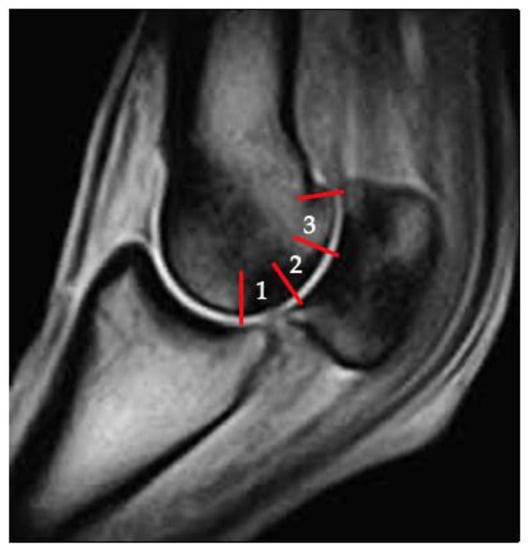

3.2. Sclerosis of the Subchondral and Adjacent Medullary Bone of the PSGs

3.4. PSG Subchondral Bone Defects

4.2. Imaging Techniques